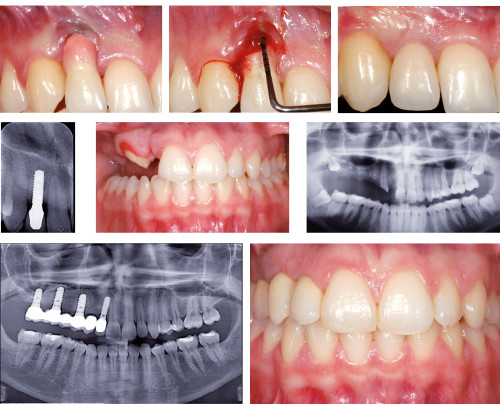

Une approche en équipe pour retrouver le sourire

La réhabilitation d’un sourire, qui plus est chez le patient parodontal, nécessite une approche pluridisciplinaire et un travail en équipe bien coordonné. En effet, le résultat esthétique dépend hautement de l’harmonie entre la gencive et la restauration prothétique. Dès lors, chaque étape du traitement a une importance majeure, depuis sa planification jusqu’à la réhabilitation prothétique en passant par la gestion des tissus mous et l’orthodontie.

L’objectif de cet exposé est de mettre en lumière la prise en charge pluridisciplinaire des réhabilitations esthétiques. Les challenges liés au patient parodontal seront mis en évidence à travers la description de plusieurs cas cliniques. L’accent sera également mis sur les nouvelles technologies et sur le choix des techniques et des biomatériaux.